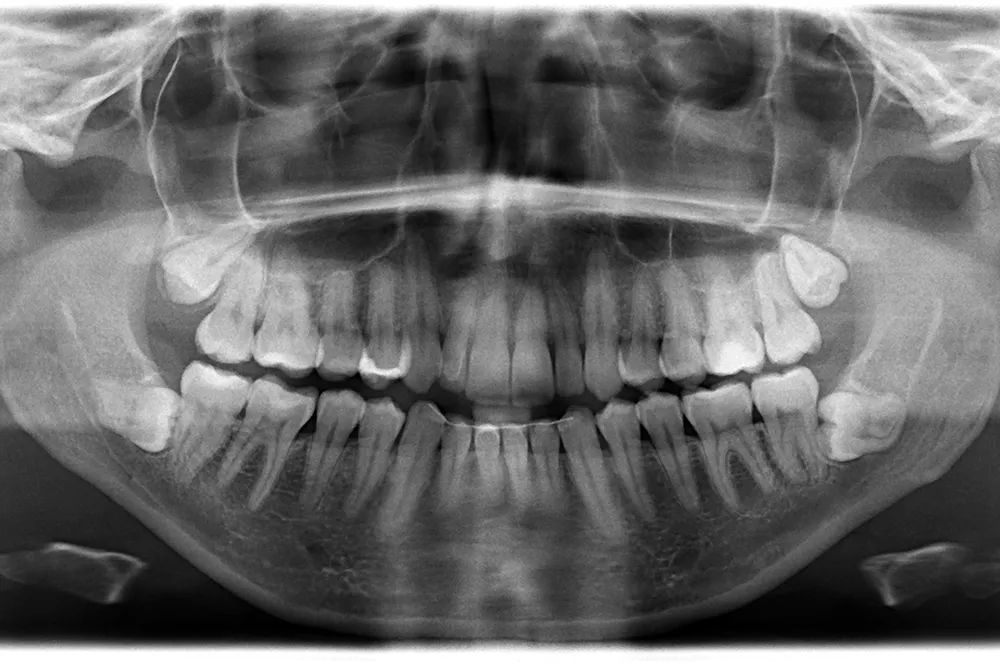

Treten diese Beschwerden regelmäßig auf oder zeigen sich im Röntgenbild problematische Zahnstellungen, empfiehlt der Zahnarzt oft eine Entfernung.

Vor einer Weisheitszahnentfernung erfolgt eine gründliche Untersuchung, meist inklusive Röntgenaufnahme, um die Lage der Zähne und die Nähe zu Nerven oder Nebenhöhlen zu bestimmen. Besprechen Sie mit dem Zahnarzt oder Kieferchirurgen: